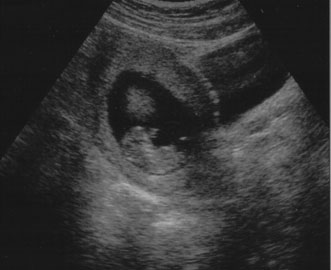

First trimester ultrasound may be performed transabdominally or transvaginally. Table 7 lists the components of a first trimester ultrasound. A crown–rump length, done between 7 and 13 weeks, can define a gestational age to within 5 days (Fig. 7).

Fig. 7. First trimester ultrasound showing crown–rump length.